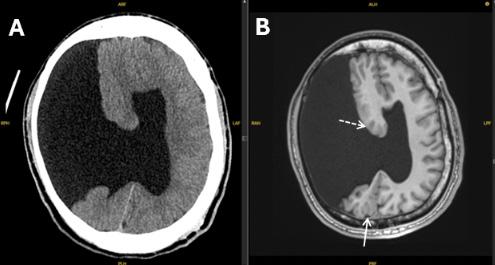

377 Undiagnosed Schizencephaly Presenting as Breakthrough Seizures

J Coacci, P Viccellio

8.BouffardJ,LaLoucheK,GierengerS,etal.Septatedascitesand cholelithiasis:anunusualclinicalpresentationforgallbladderrupture. JDiagnMedSonogr. 2002;18(2):84–6.

9.JainS,PhatakS,DeshpandeS,etal.Septatedascites:animportant signoftubercularperitonitis. JDattaMegheInstituteofMedical SciencesUniversity. 2021;16(3):596.